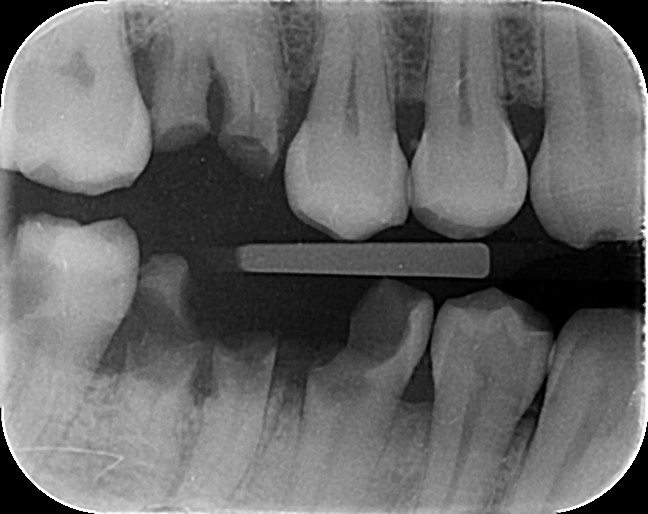

4. In the X ray bellow for which jaw periodontal bone loss is evident?